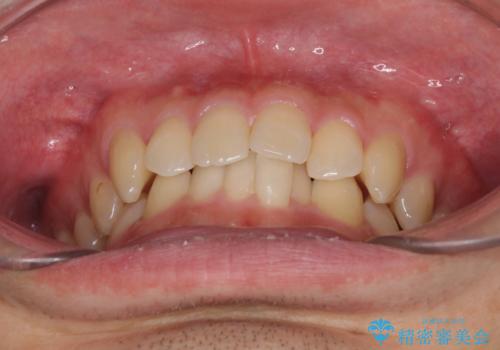

前歯の咬み合わせとデコボコを解消 インビザラインによる矯正治療

- 上下前歯のデコボコと深い咬み合わせを気にして来院された患者様です。

インビザラインによる上下歯列の拡大と、IPR(歯と歯の間を削る)にるスペースの獲得により、前歯のデコボコとディープバイトを改善することとしました。

もう少し下の前歯を整えたかったのですが、患者様の治療を早く終了させたいという希望により、細かい叢生を残しての終了となりました。